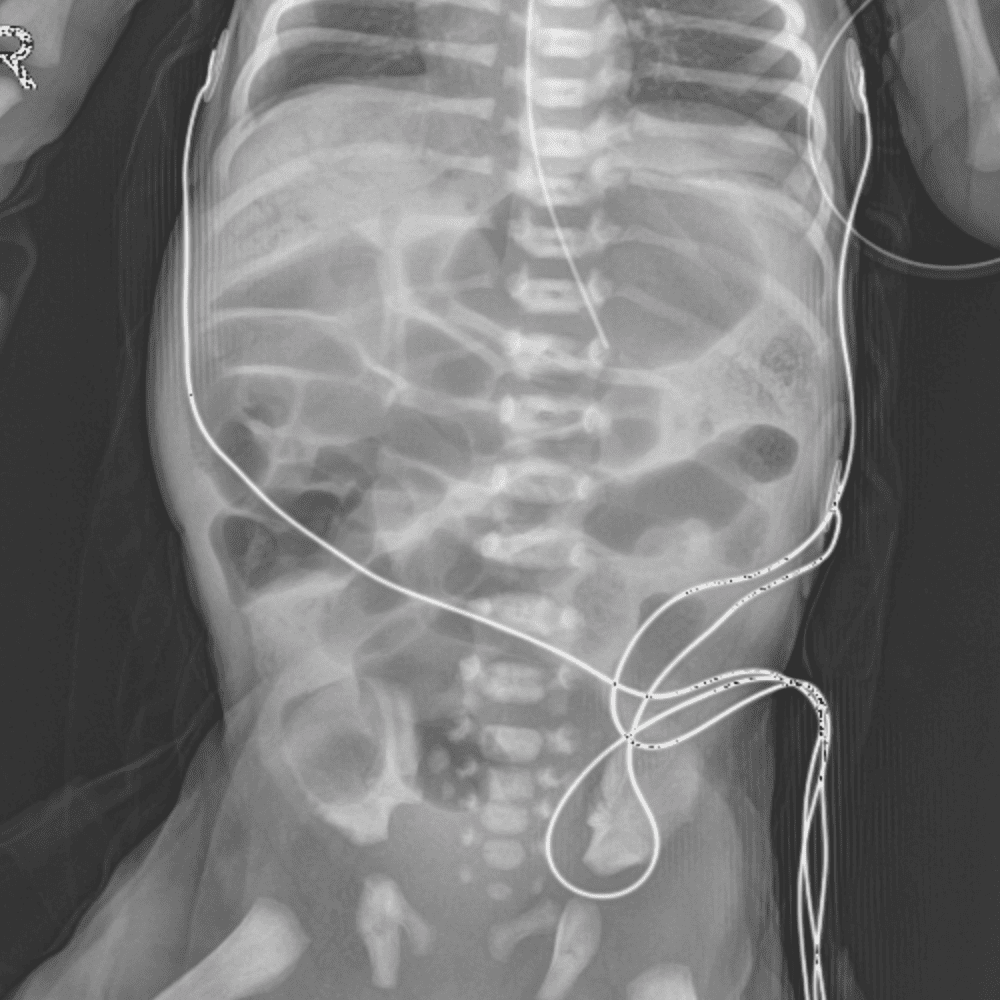

Peds Abdomen

Practice

Simulates call by including subtle or difficult cases and some normals.

30 cases